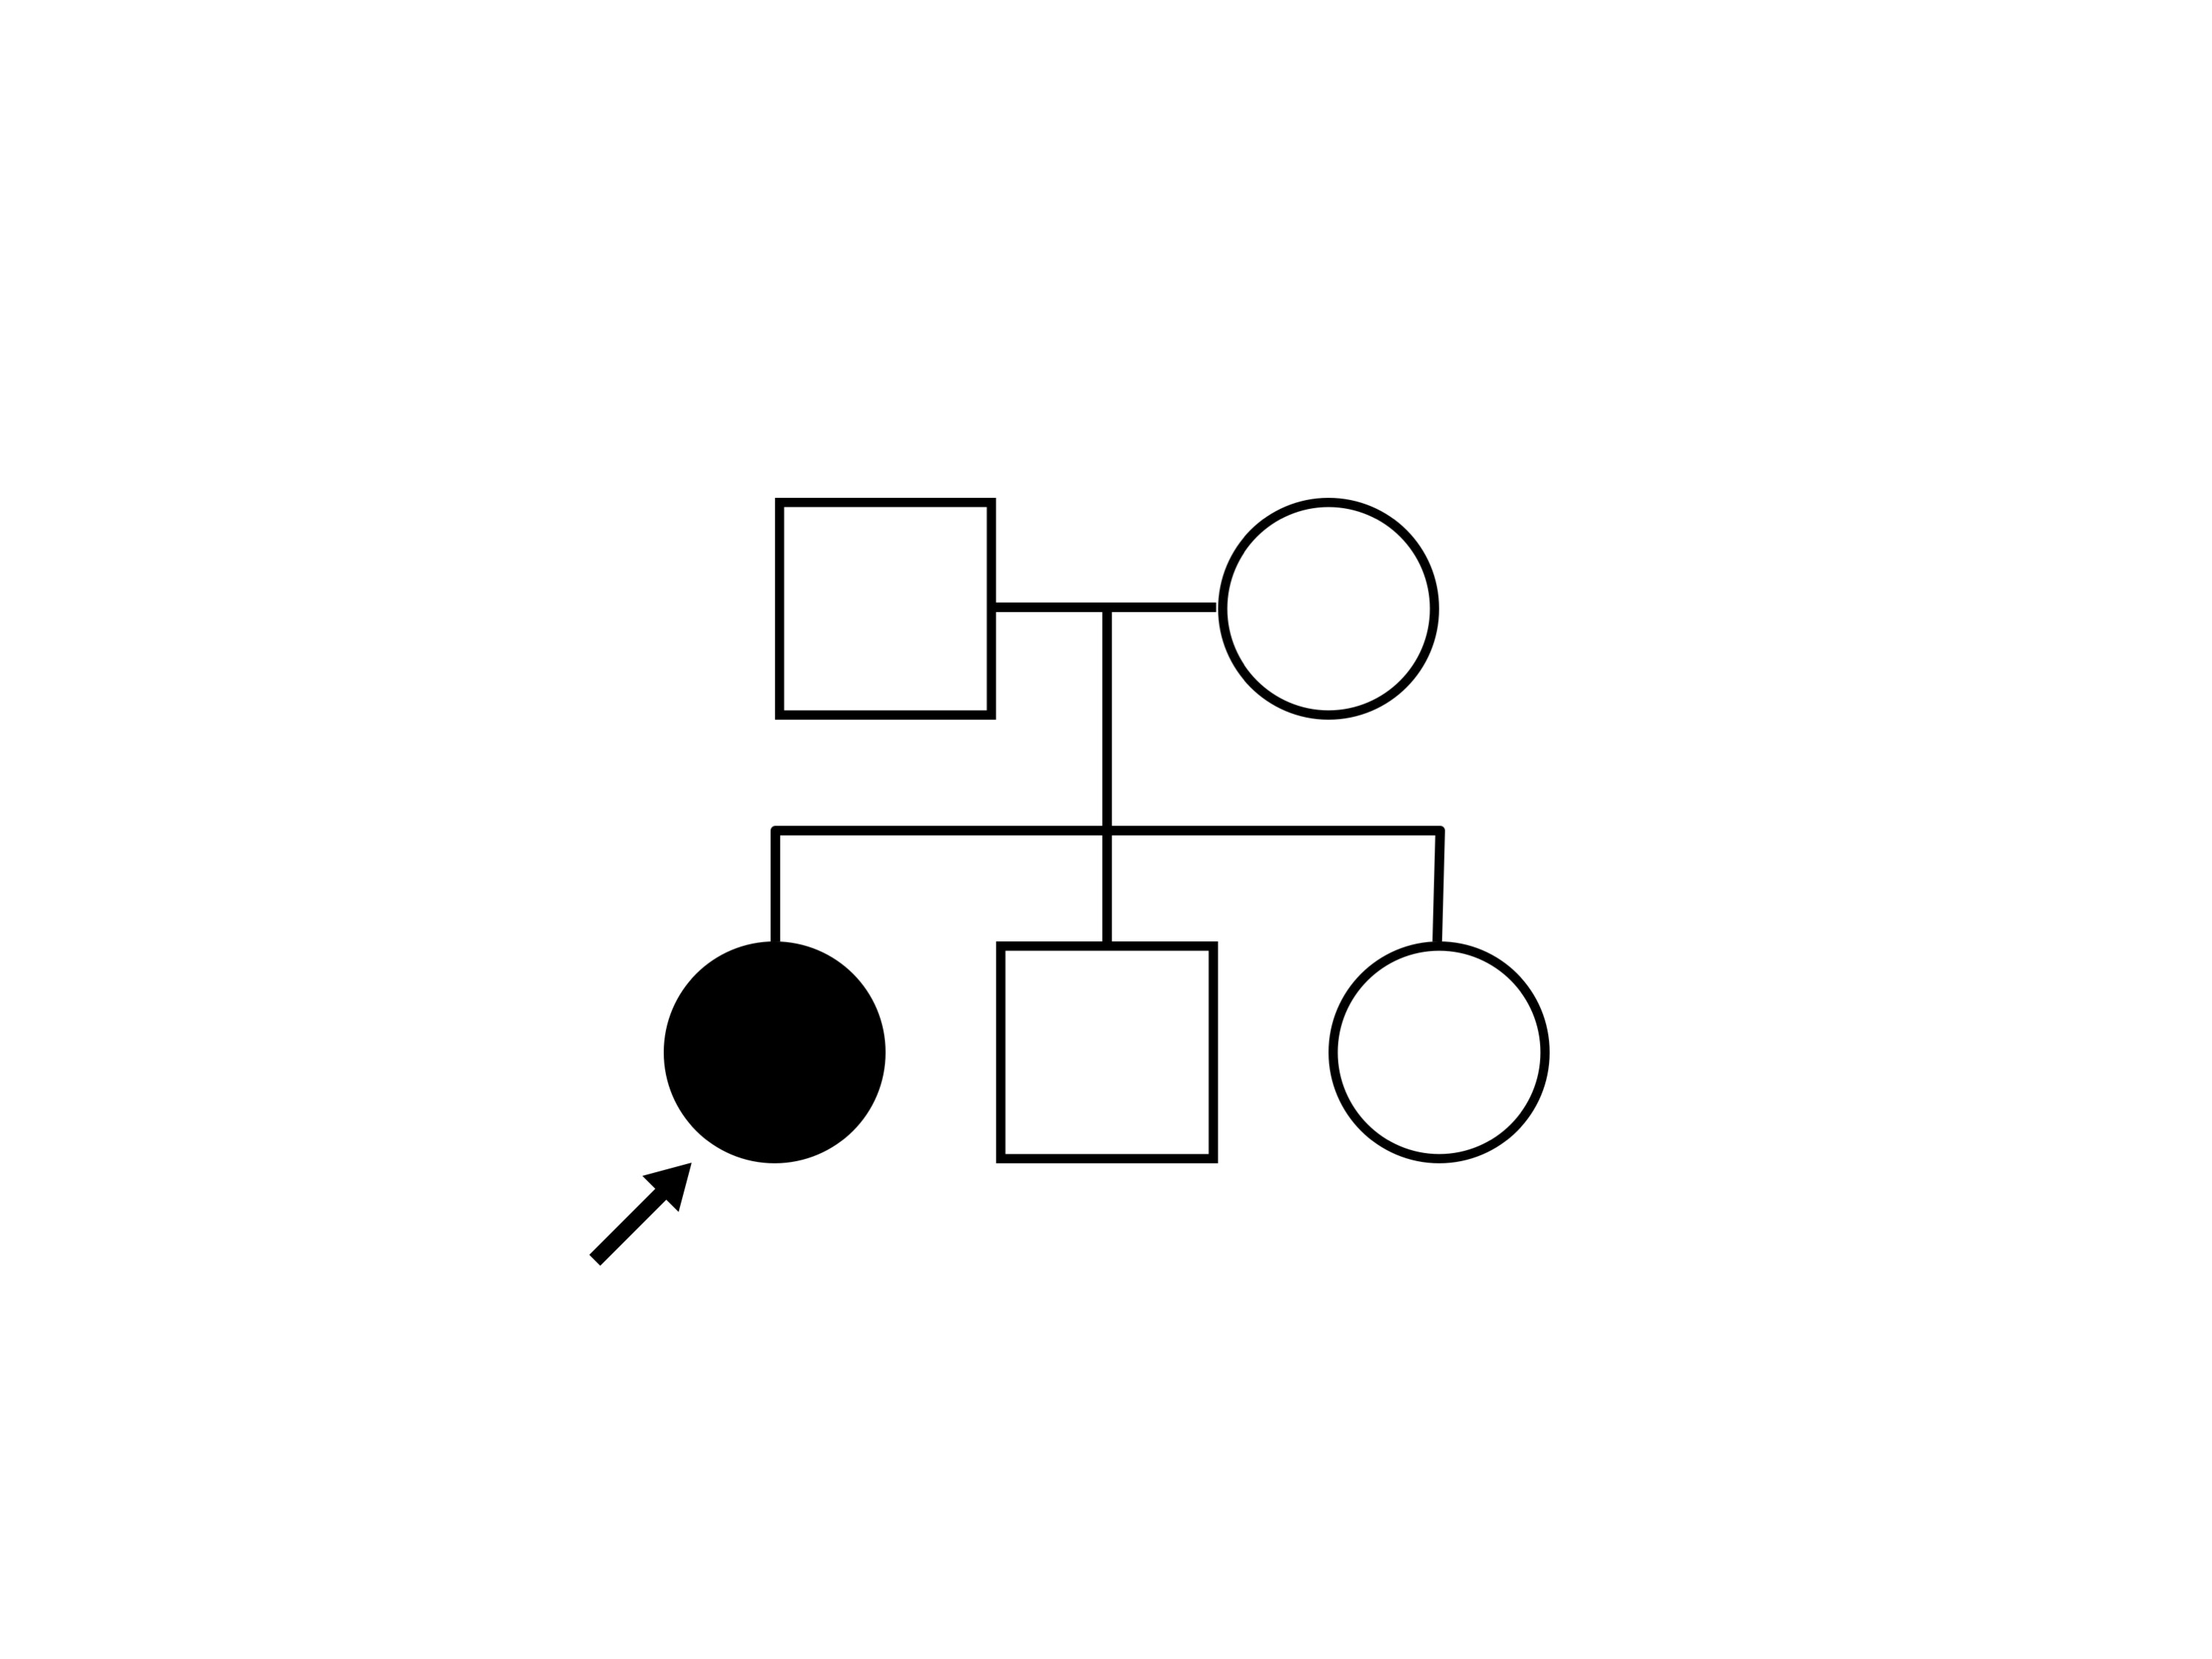

Congenital Stationary Synaptic Dysfunction (IA2g)

Congenital Stationary Synaptic Dysfunction (IA2g)

| Congenital Stationary Synaptic Dysfunction | CABP4 | Arg49Stop CGA>TGA | IVS1+1 G>T | AR |

Inheritance:

AR